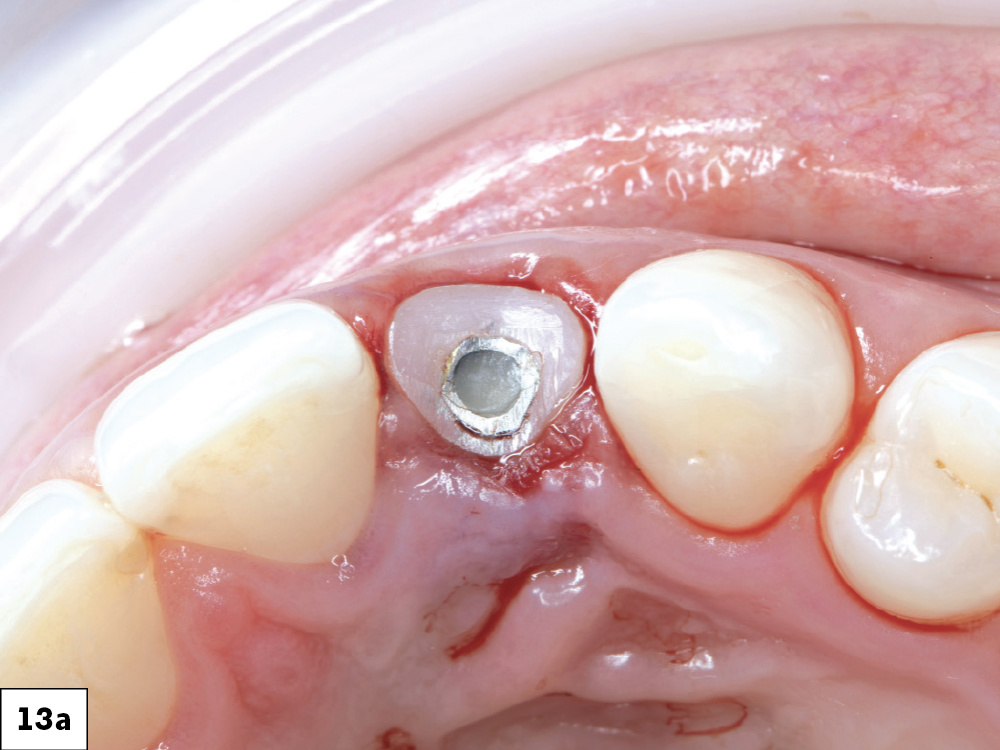

Figures 13a, 13b: The emergence profile created by the custom healing abutment is crucial for maintaining the gingival architecture, ensuring proper alignment of the papilla, margins, and soft tissue. The healing abutment helps retain the patient’s natural tooth appearance as closely as possible throughout the healing process.